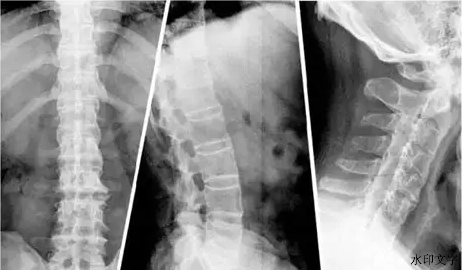

在医学影像的世界里,一颗罹患强直性脊柱炎(AS)的脊柱,晚期会呈现出一种独特的形态:原本一节节独立、灵活的椎体,因炎症的反复侵袭和身体的自我修复,最终像竹子一样节节融合,连成一根僵硬的“竹节”。

(3)无奈的融合:经年累月,这些多余的骨赘在椎体之间搭起“桥梁”,最终导致关节与关节融合,脊柱失去活动能力,如同竹节。